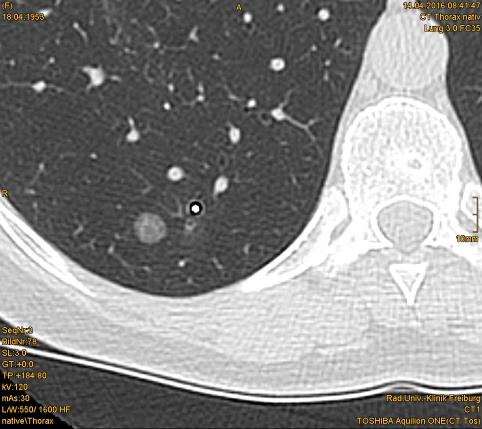

CT Thorax: Goldmarker platziert in unmittelbarer Nähe eines kleinen flauen Rundherdes im rechten Lungenunterlappen.